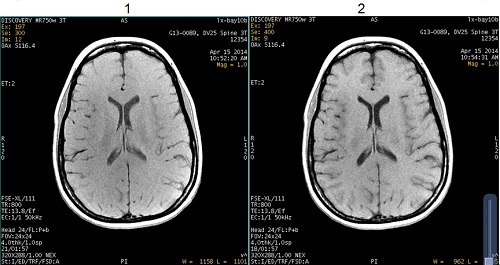

FSE T1 Optimization

Use FSE T1 Optimization to optimize the T1 contrast in brain and spine images acquired with 2D FSE T1 pulse sequences.

| Number | Description |

|---|---|

| 1 | FSE T1-weighted image |

| 2 | FSE T1-weighted image with FSE T1 Optimization |

The User CV applies a +90° RF pulse at the end of the echo train that results in a darker signal from fluids thus improving T1 contrast when compared to a conventional FSE sequence. In addition, the scan time may be decreased when compared to a SE T1 sequence.